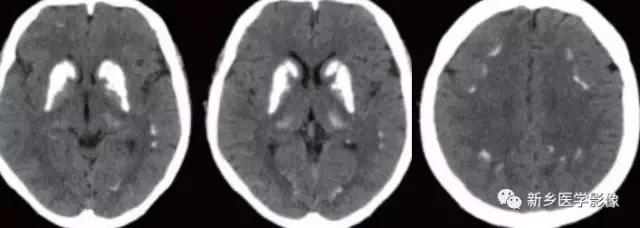

TORCH综合症是病毒或原虫感染脑组织引起脑炎。包括弓形体原虫、风疹病毒、巨细胞病毒、疱疹病毒,以疱疹病毒最为常见。主要发生于胚胎期或分娩过程中,故又称先天性宫内感染或先天性TORCH感染。

巨细胞病毒感染引起的钙化常位于脑室周围,可引起胎儿脑发育畸形,如巨脑回畸形、多小脑回畸形、无脑回畸形。

弓形体原虫感染引起的钙化常靠外围,可散在分布于脑实质,往往引起中脑导水管狭窄。